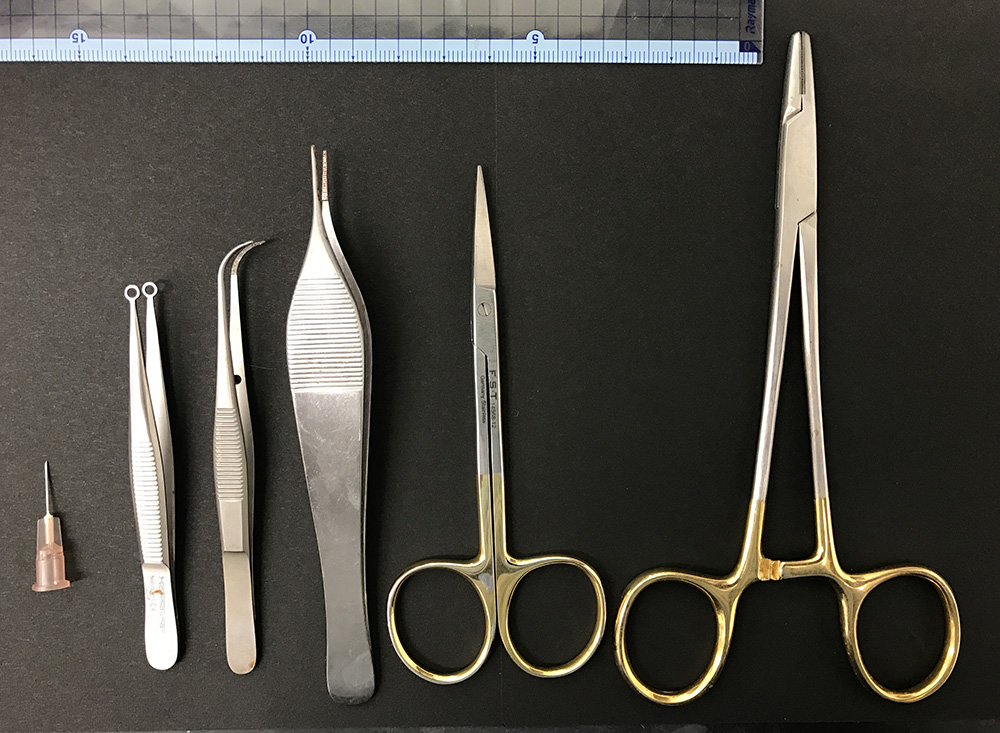

- Operating scissors and tweezers (see Figure 1)

Figure 1. Surgical instruments used in this protocol